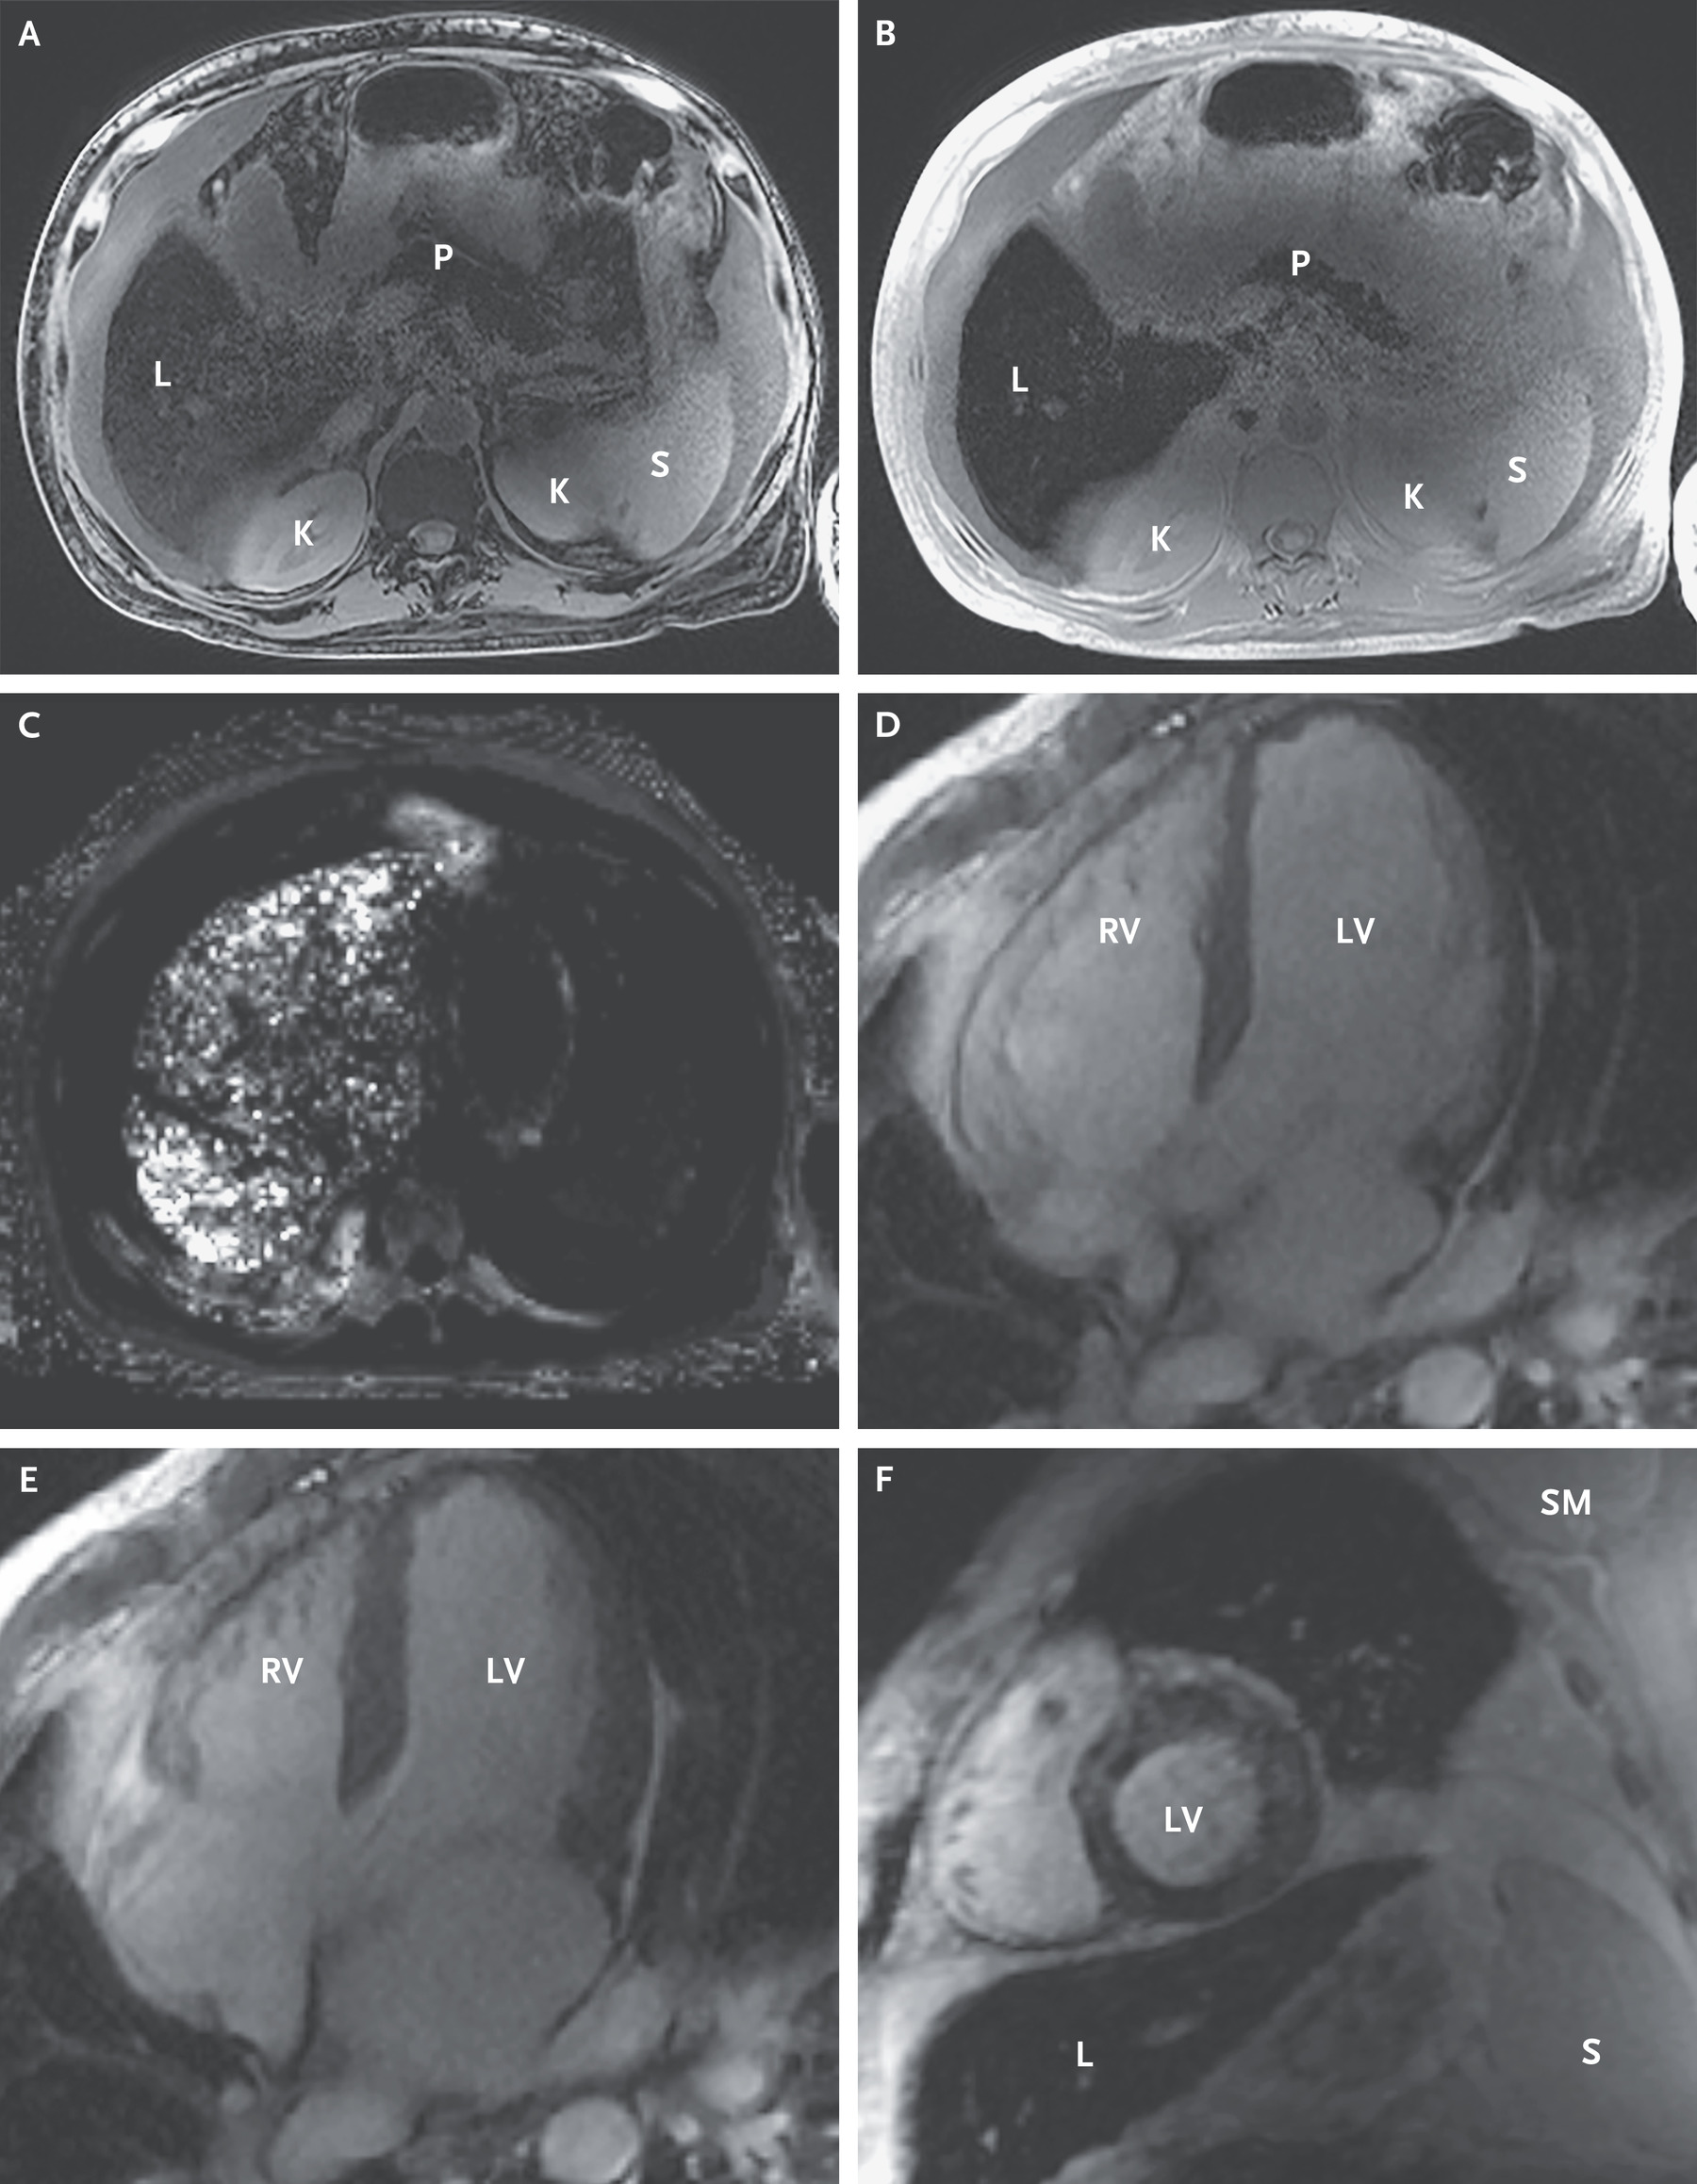

of abdominal (panels A, B, & C), cardiac (panels D & E), and abdominal/cardiac (panel

F) MRIs are shown below.

K, kidney; L, liver; LV, left ventricle; P, pancreas; RV, right ventricle; S, spleen.

The presented case had iron deposits in his liver, heart, pancreas, joints,

and pituitary gland with consequent development of micronodular cirrhosis, myocardopathy

with CHF, type II diabetes mellitus, arthritis, and hypothyroidism. He had elevated

levels of ferritin (3543 ug/L), iron (272 ug/dL), and transferrin saturation (96%).

On biopsy, the liver was nodular with marked iron deposition in hepatocytes and bile

ducts.